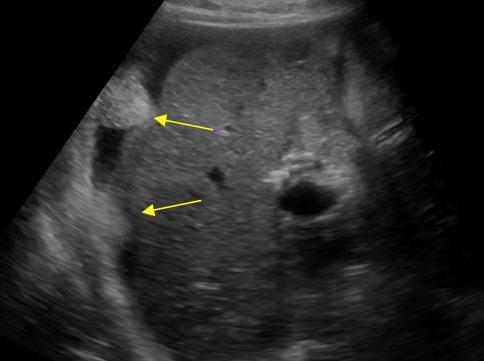

Di căn phúc mạc

» Thông tin: Nữ giới – 55 tuổi.

» Lâm sàng: Đau bụng / K buồng trứng.